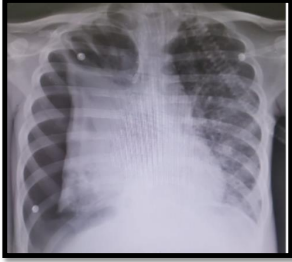

Analise a radiografia abaixo e responda

Assinale a alternativa que apresenta o tratamento imediato que deve ser proposto para este caso.